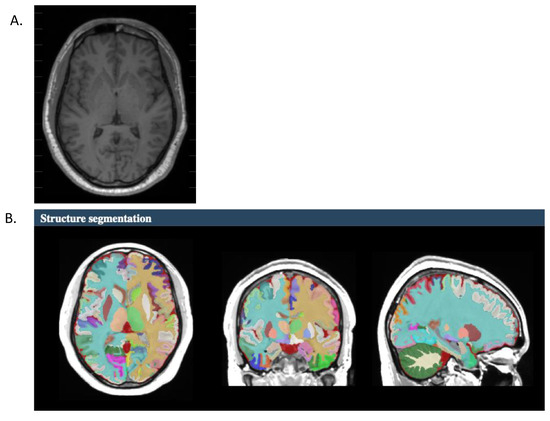

2.3. Segmentation Measurements

- Manjón, J.V.; Coupé, P. volBrain: An online MRI brain volumetry system. Front. Neuroinform. 2016, 10, 30. [Google Scholar] [CrossRef] [PubMed]

- Manjón, J.V.; Romero, J.E.; Vivo-Hernando, R.; Rubio, G.; Aparici, F.; de la Iglesia-Vaya, M.; Coupé, P. vol2Brain: A new online Pipeline for whole Brain MRI analysis. Front. Neuroinform. 2022, 16, 862805. [Google Scholar] [CrossRef] [PubMed]